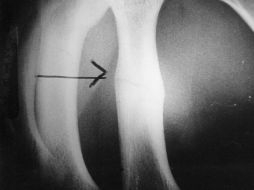

Suplementos Fracturas por osteoporosis pueden ser incapacitantes 27 de octubre de 2016 - 12:53 hs Enfermedades Osteoporosis